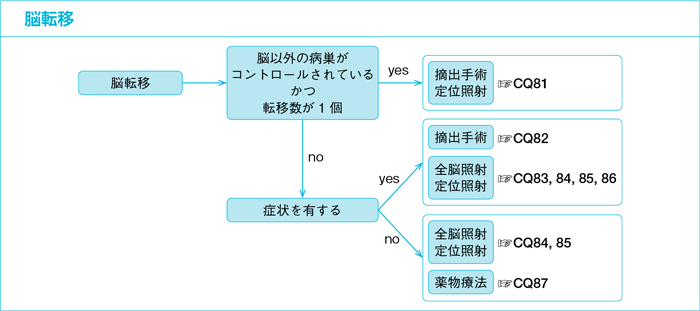

脳転移 転移性脳腫瘍 でもあきらめない 10年生存例の解析 がん

脳転移 転移性脳腫瘍 でもあきらめない 10年生存例の解析 がん